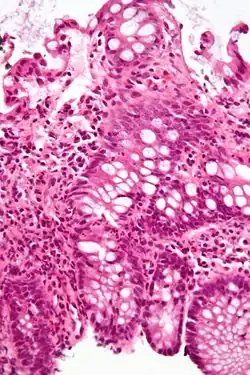

| A micrograph demonstrating cryptitis, a microscopic correlate of colitis. H&E stain. | |

An important investigation in the assessment of colitis is biopsy for histopathology. A very small piece of tissue (usually about 2mm) is removed from the bowel mucosa during endoscopy and examined under the microscope by a histopathologist. A biopsy report generally does not state the diagnosis, but should state any presence of chronic colitis, give an indication of disease activity, as well as state the presence of any epithelial damage (erosions and ulcerations).[6]

Histopathology findings generally associated with chronic colitis include:[6]

-

Crypt degeneration -

Crypt branching and other architectural distortions -

Paneth cell (pictured) or gastric metaplasia (only applies in the left colon and rectum)

Other findings include basal plasmacytosis and mucin depletion.[6] Histopathology findings generally associated with active colitis include:[6]

Neutrophilic cryptitis (neutrophils within crypt epithelium) -

Crypt abscesses (luminal neutrophilic aggregates) -

Gland destruction -

Ulceration (seen here as absence of epithelium, and granulation tissue with many fibroblasts)